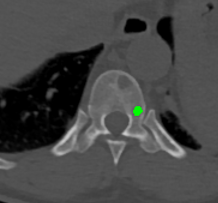

Figure 2: Qualitative results of bone lesion detection. Each column shows a cropped slice with the top row displaying ground-truth (green) and the bottom row showing nnUNet predictions (yellow). (a) shows a TP osteolytic lesion; (b) shows the prediction of a real osteoblastic lesion that was not prospectively marked as ground-truth (before review), and after GT review, it was correctly considered as ground-truth; (c) shows an osteolytic lesion not annotated in ground-truth before review and correctly marked afterwards. A FN adjacent to it is also shown. (d) shows a rare FP on the cortex of a rib.

Results. Qualitative and quantitative results of our model are presented in Fig. 2 and Table 1 respectively. Our model achieved a precision of 96.7% and a recall of 47.3% for detection of bone lesions (lytic, blastic, and mixed). We observed that the model was very confident in its predictions as demonstrated by the vast number of actual lesion predictions (TPs) compared against the FPs. Despite the high precision, the model was not very sensitive to the detection of bone lesions due to the large number of FNs.

In this pilot work, we proposed to automatically detect bone lesions in CT volumes via a proxy segmentation task using the 3D full-resolution nnUNet model. Despite the partial and incomplete 3D annotations used to train the model, it was very precise in its predictions (96.7%). Due to the nature of the weak 3D annotations, the middle slices of the predictions provided better delineations of lesions in contrast to the adjacent slices (which were only coarse bounding boxes). These results were obtained after a thorough qualitative review of the model’s predictions. Initially, the test split also comprised of only prospectively marked lesions with other potential lesions being left unmarked. We noticed that the model captured lesions that were not originally annotated by the reading radiologist. Despite the vast majority of the predictions that were considered as FPs were, in fact, real lesions (TPs), the precision and recall languished at 25.6% and 50.2% respectively as shown in Table 1 (Before GT review). The discordance between the initial quantitative and qualitative results spurred us towards a full review of our ground-truth annotations in the test split. Post completion of the review, the recomputed metrics resulted in a significant increase in the precision of our model, which was in line with the observed qualitative results.